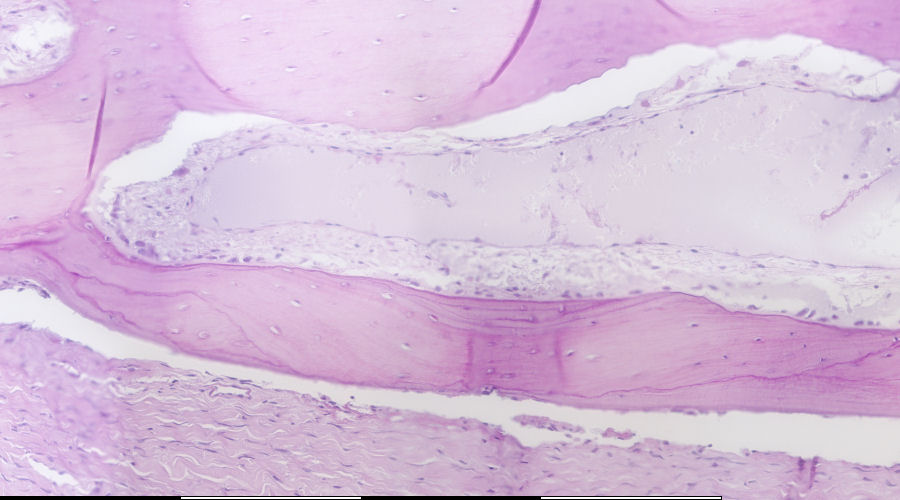

Bone-remodeling unit